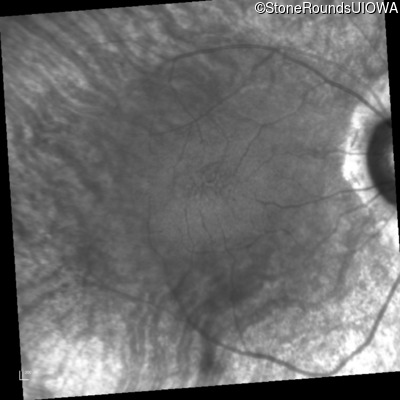

Age at visit: 49 years (Visit 2)